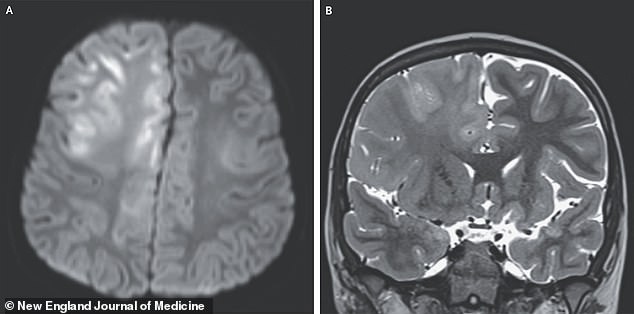

But for some, the damage is far more insidious. A case study published in the *New England Journal of Medicine* details the story of a seven-year-old boy in California. He had suffered seizures and cognitive decline for months. His reflexes were spasming, and he could no longer speak. An MRI revealed brain swelling and signs of cell death. Doctors diagnosed him with subacute sclerosing panencephalitis (SSPE), a rare but deadly complication of measles. The boy had been infected as a baby in Afghanistan, where measles is common. He died a year later from SSPE, a condition with a 95% mortality rate.